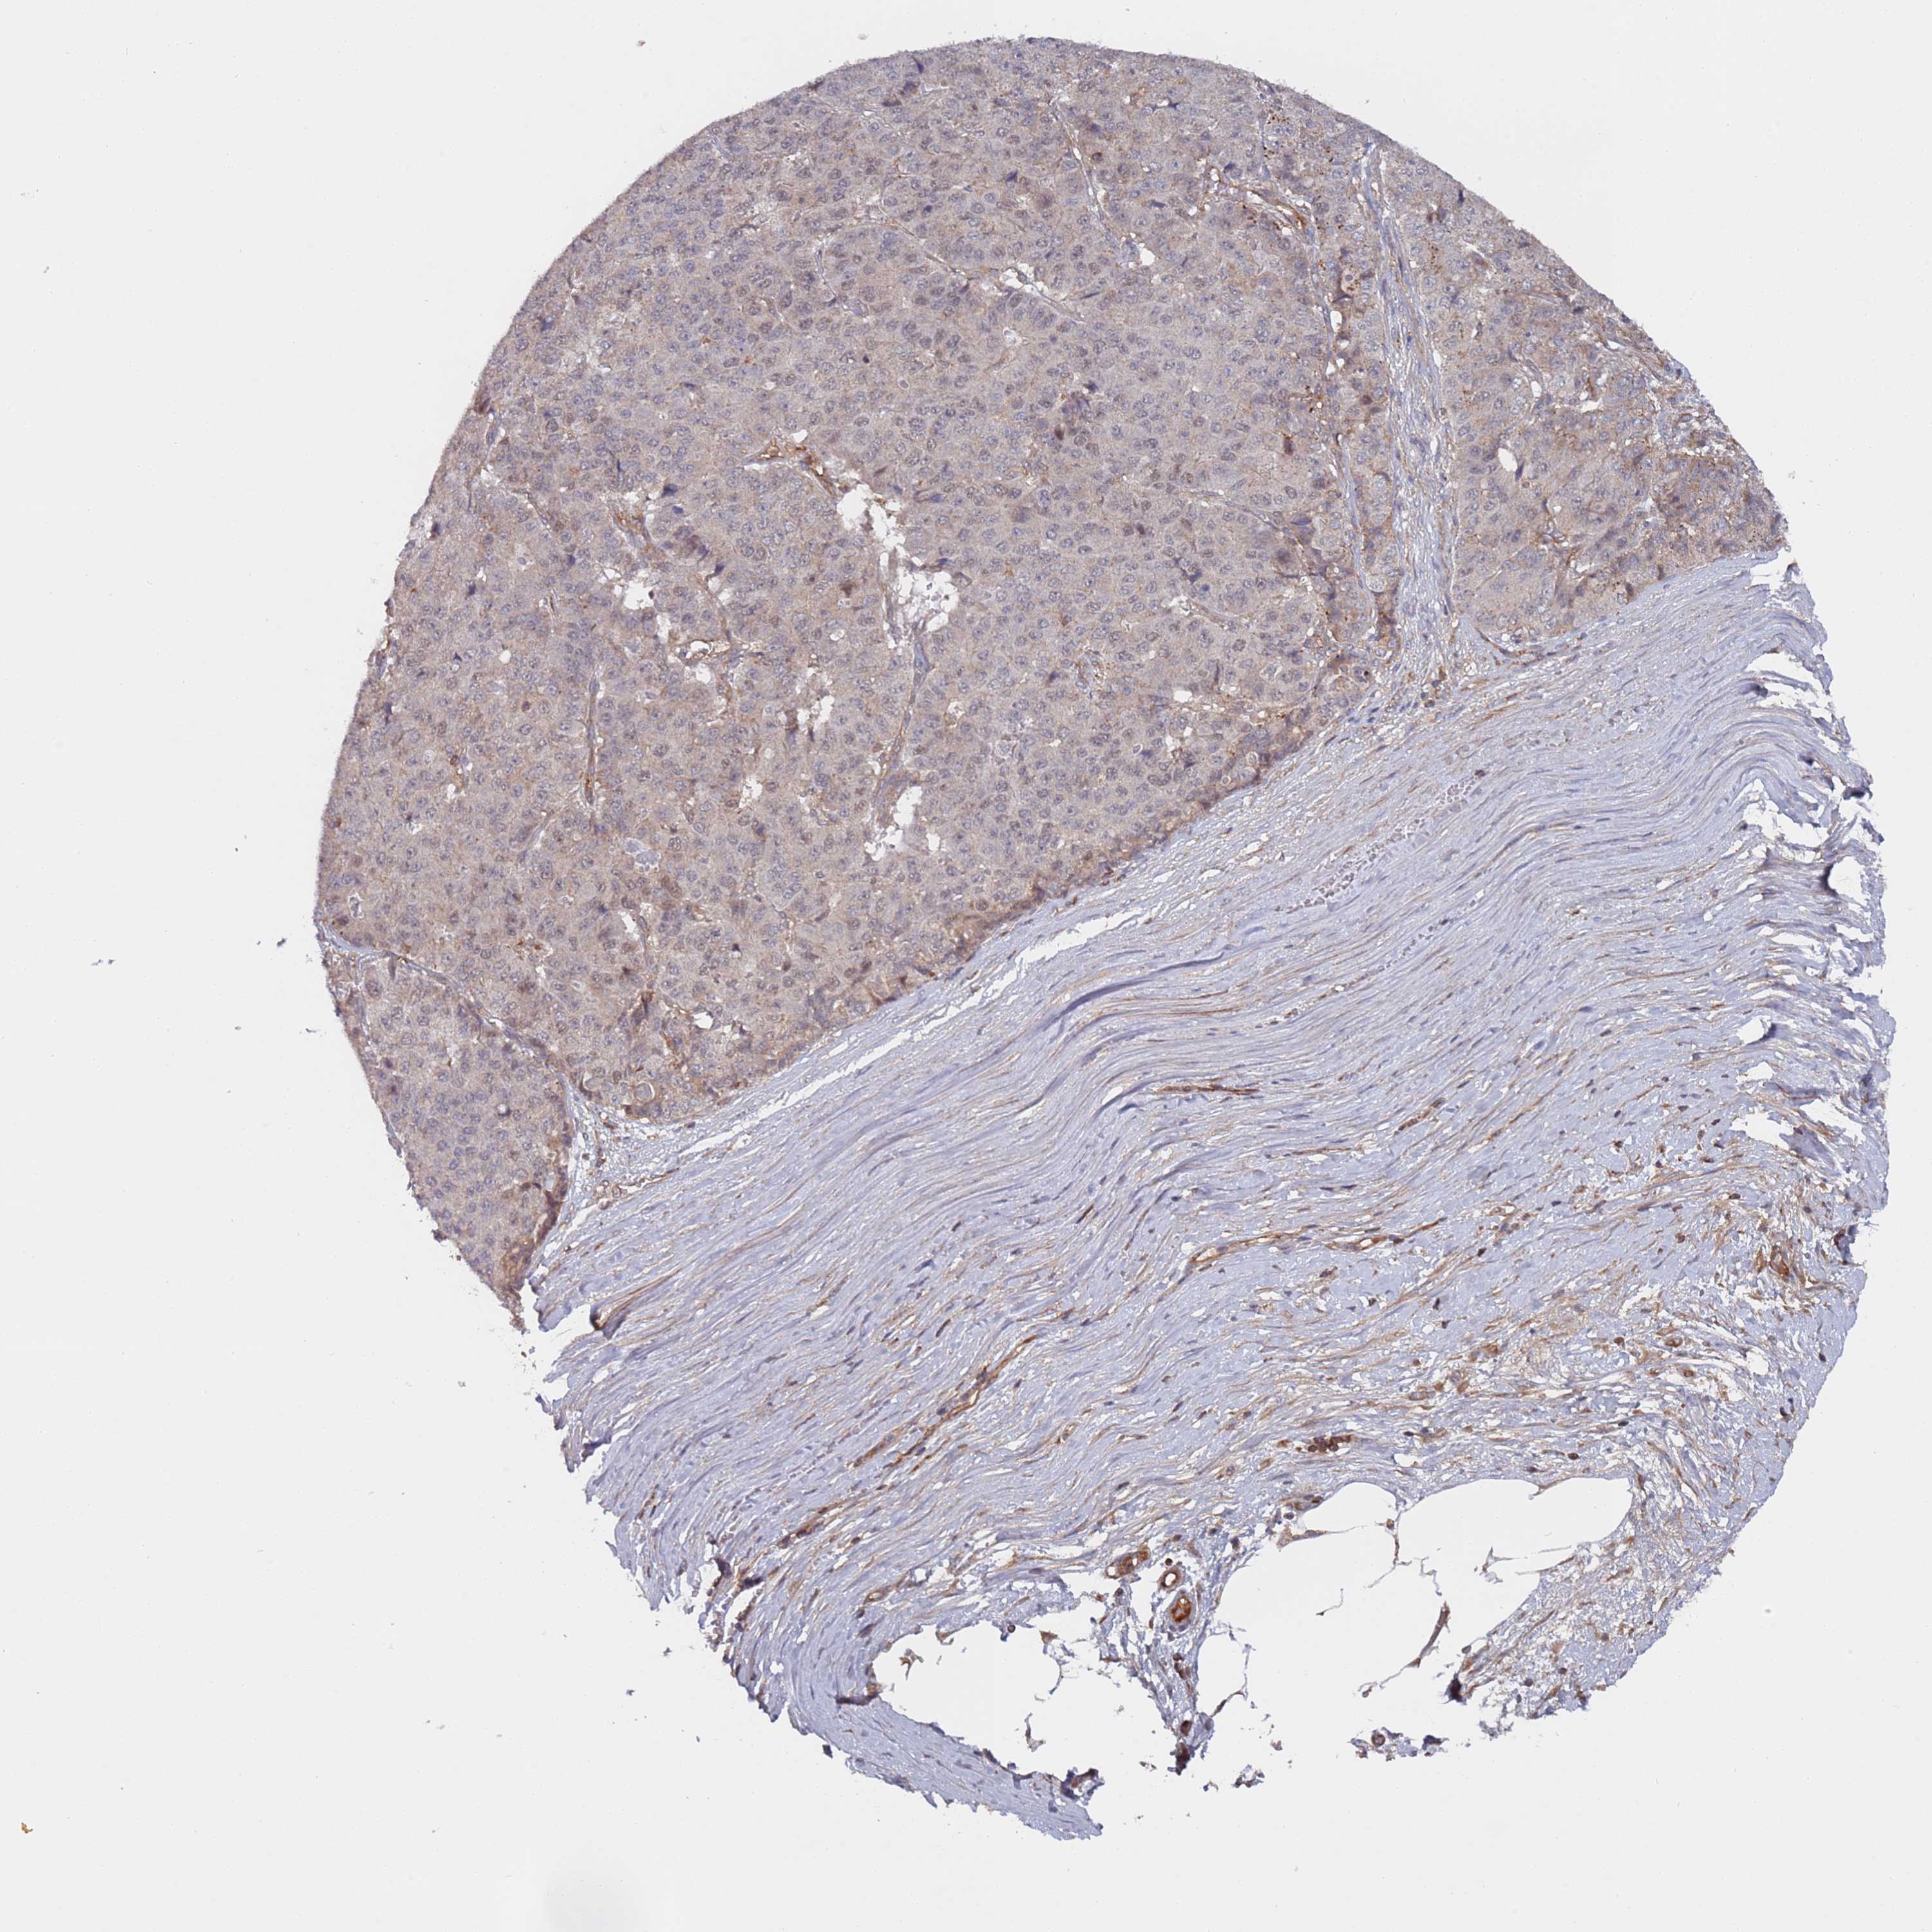

PANCREATIC CANCER - Protein expressioni

A mouse-over function shows sample information and annotation data. Click on an image to view it in a full screen mode. Samples can be filtered based on level of antibody staining by selecting one or several of the following categories: high, medium, low and not detected. The assay and annotation is described here.

Note that samples used for immunohistochemistry by the Human Protein Atlas do not correspond to samples in the TCGA dataset.

Antibody stainingi

Antibody staining in the annotated cell types in the current human tissue is reported as not detected, low, medium, or high, based on conventional immunohistochemistry profiling in selected tissues. This score is based on the combination of the staining intensity and fraction of stained cells.

Each image is clickable and will lead to virtual microscopy that enables deeper exploration of all samples and also displays staining intensity scores, fraction scores and subcellular localization as well as patient and tissue information for each sample.

Antibody HPA046952

Staining

High

Medium

Low

Not detected

Intensity

Strong

Moderate

Weak

Negative

Quantity

>75%

75%-25%

<25%

None

Location

Nuclear

Cytoplasmic/membranous

Cytoplasmic/membranous,nuclear

Adenocarcinoma, NOS